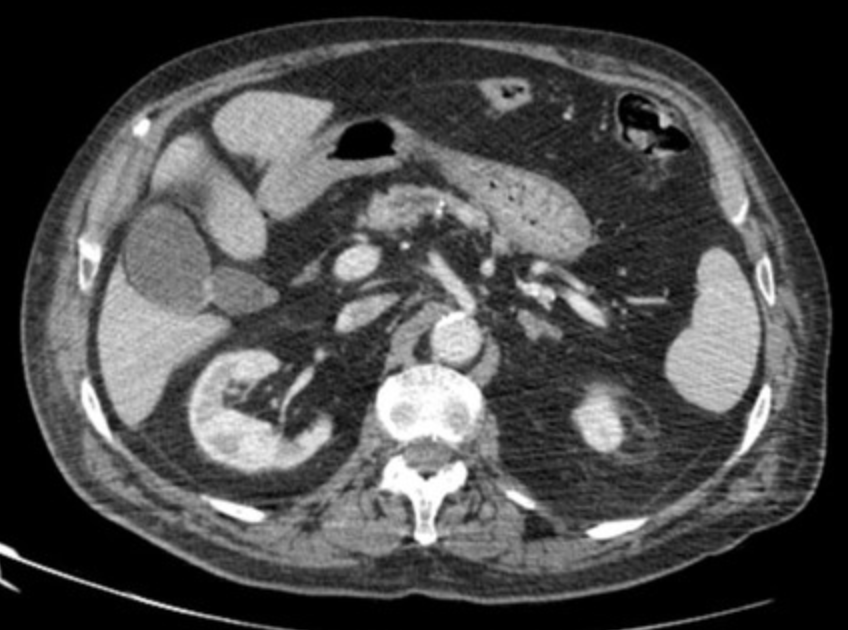

Klatskin Tumor (Hilar Cholangiocarcinoma)

• Typically at bifurcation of common bile duct

• Findings

• Intrahepatic biliary ductal dilation

• Mass at liver hilum